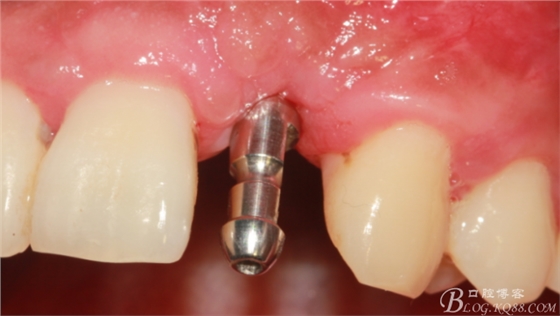

10天拆線一切正常,又過了兩周患者復(fù)診,自述期間無異常??趦?nèi)檢查,真的嚇了一跳,唇側(cè)鼓了個(gè)包,擠壓有白色分泌物溢出,絕對(duì)不是膿液,液體排除后,術(shù)區(qū)觸診空虛,外觀塌陷。這時(shí)候考研大夫的時(shí)刻到了,是先觀察一段時(shí)間再說?還是馬上進(jìn)行處理?我的回答是:馬上處理!如果你沒有及時(shí)處理,而是放患者回家觀察,那么接下來會(huì)發(fā)生如下情況:1.回家后患者家屬及親友會(huì)有很多你可以想象得到的討論;2.患者及家屬會(huì)對(duì)你產(chǎn)生不信任,勢(shì)必會(huì)到其他門診或醫(yī)院檢查,他院大夫會(huì)不會(huì)發(fā)表對(duì)你不利的言論;3甚至?xí)蚁嚓P(guān)法律界人士找你討要說法。

于是我果斷告知患者,手術(shù)失敗了,不能拖延,如不及時(shí)處理,炎癥繼續(xù)發(fā)展會(huì)很快波及鄰牙牙槽骨。患者接受我的建議。切開翻瓣,骨粉及生物膜消失了,骨吸收嚴(yán)重,幸運(yùn)的是,因?yàn)樘幚砑皶r(shí),鄰牙骨支持依然存在。